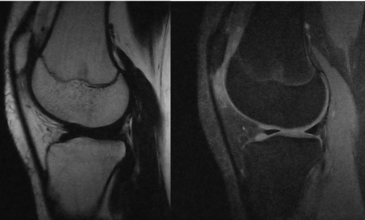

Altersfeststellung mittels MRT-Gelenkscanner

In dem Projekt “Altersfeststellung mittels MRT-Gelenkscanner” werden die aus dem Vorgängerprojekt gewonnen Ergebnisse an einer größeren Fallgruppe validiert.